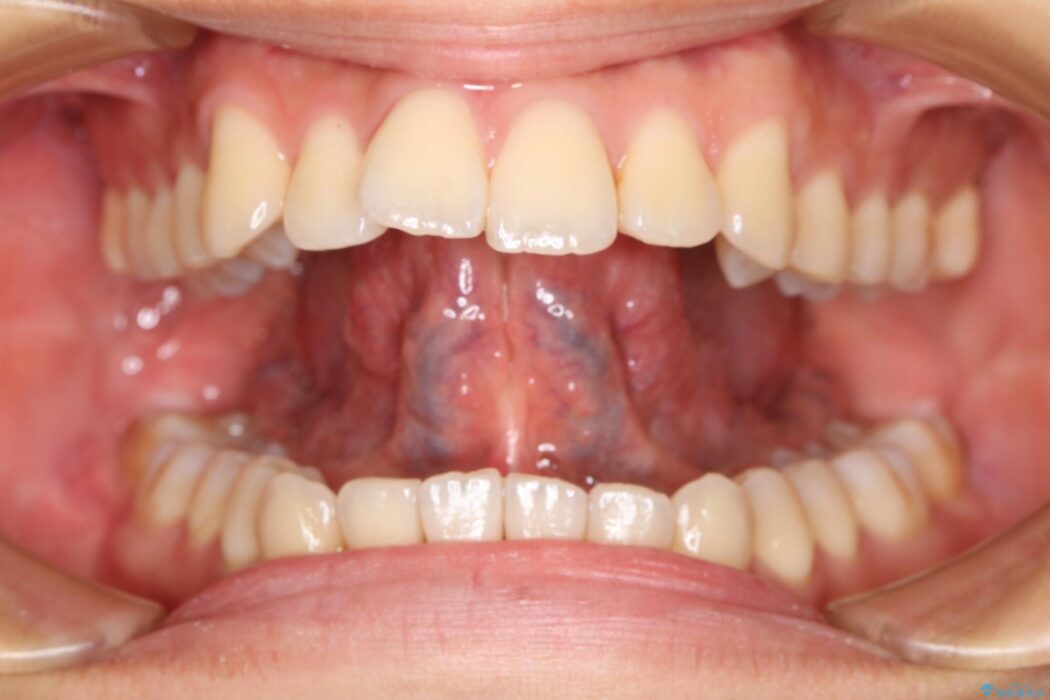

【20代男性】滑舌の悪さを改善したい!舌小帯切除術

滑舌の悪さを治したいとの主訴で来院、舌小帯切除術をご希望されました。

舌小帯は舌の下面についているヒダのことを指します。個人によっても違いますが、舌小帯が短い・硬い場合は舌の動きが制限されてしまいます。それによって滑舌の悪さ、摂食・嚥下に影響を及ぼすことがあります。

このような舌小帯の異常の場合、「舌小帯切除術」を行うことがあります。

本症例ではレーザー機器を用いて手術を行いました。これにより従来のメスを使用する術式と比べて所要時間の短縮が図れ、かつ縫合を必要としないため術後の不快感も軽減することができます。